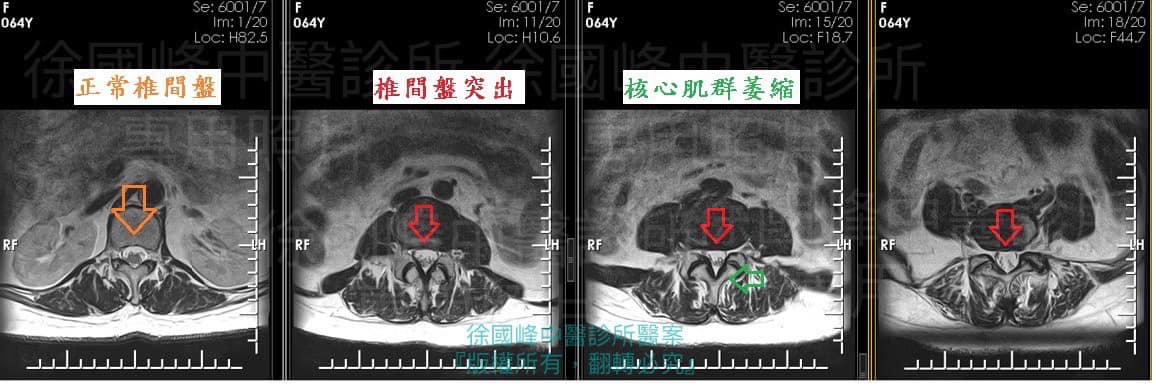

X光跟核磁共振都顯示有骨刺跟椎間盤突出,但並不特別嚴重,但為什麼會那麼痛,還痛到每天吃兩次止痛藥,答案是剛剛好卡住神經根,又發現患者髖關節張力過大,這種情況會讓患者雖然核磁共振看起來都沒有什麼大問題,但是走路一段時間會因為髖關節的張力拉扯到腰椎的腰大肌,進一步讓神經根拉扯

1.腰椎核心肌群萎縮

2.L5S1輕微椎間盤突出